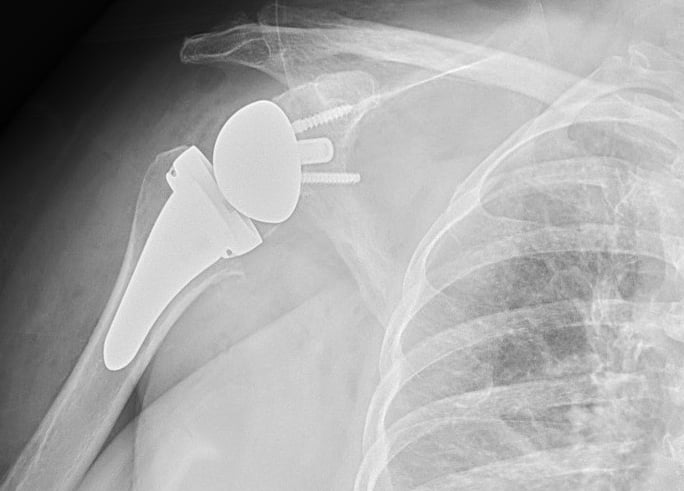

Chirurgia di Spalla e Gomito

Eseguo visite specialistiche, trattamenti conservativi e interventi specialistici sulla spalla e sul gomito, sia artroscopici sia a cielo aperto, per il trattamento delle principali patologie ortopediche e traumatiche di queste articolazioni.

Artrosi di spalla (Gleno-Omerale)